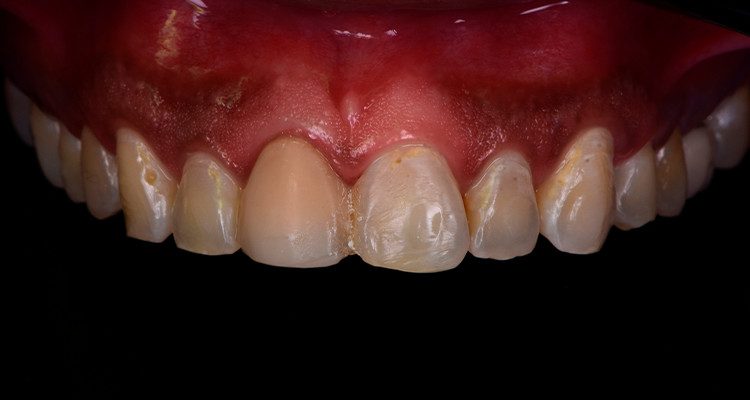

Ao procurar atendimento clínico, foi verificada restauração extensa no dente 11 devido a alteração de cor da resina composta associado à restauração insatisfatória.

2 | Imagem intraoral frontal da arcada superior.